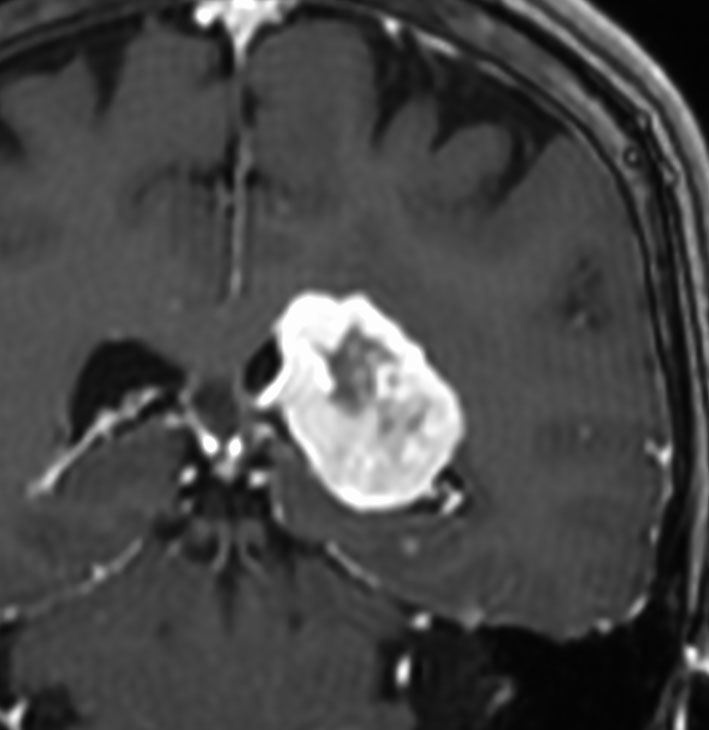

大脳鎌テント接合部髄膜腫 falcotentorial meningioma

30代の女性に発生した髄膜腫です,一見すると松果体細胞腫と見分けはつきません。右の画像に見られるように典型的な中脳水道狭窄を生じていました。

軽度の閉塞性水頭症もありますが,頭痛も無く無症状なので経過を観察しました。髄膜腫だと診断できるのは,右の画像で見られるようにガレン大静脈が右側に偏っているからです。松果体細胞腫の場合は,ガレン大静脈は上方に変位します。

1年間経過観察したら水頭症が進行して脳室が拡大,腫瘍のサイズも大きくなりました。右側の画像で見られるようにガレン大静脈の左側のテントの下面から発生した髄膜腫でした。

左は手術直後の画像です,手術は左側のテント下面を見るために,後頭部経テント法 OTA occipital transtentorial approach で,小脳テントの左側を切断して腫瘍を全摘出しました。右側は6年後の画像ですが,腫瘍再発はありません。

「注意」症状のない患者さんには,なかなか勧められないリスクの高い手術です。この患者さんの場合は無症状で水頭症も軽度で経過観察をしたのですが,本当はそうしてはならないものでした。閉塞性水頭症が急激に悪化して,急性水頭症のために意識障害になる可能性があるものです。